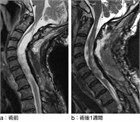

1. 脊髄空洞症の原因として頻度の高いChiari奇形に関するガイドラインが2023年に米国脳神経外科コングレス(Congress of Neurological Surgeons(CNS))より提唱され、治療に関しては、大孔減圧術が第一選択だが、小脳扁桃への操作の併用も症状改善や空洞縮小に寄与する可能性があること、6~12か月後で空洞が縮小しない場合は追加手術を検討してもよいこと、術後症状が改善しても症状の確認や画像検査によるフォローアップが望ましい可能性があること、などが記載されたため、それに応じて加筆を行った[1][2][3]